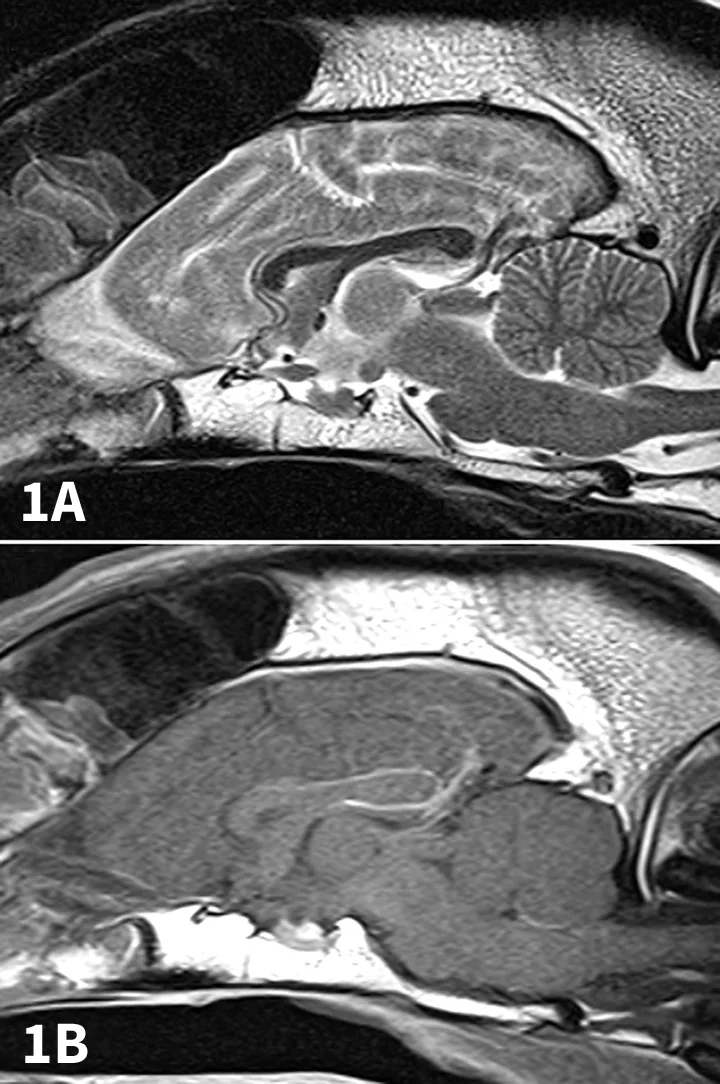

Figure 1

T2-weighted sagittal (A) and contrast-enhanced T1-weighted sagittal (B) MRI scans of a normal dog.

MRI disclosed multiple intra-axial contrast-enhancing lesions with a generalized random distribution throughout the brain with specific involvement of the cerebellar nuclei, peripheral cerebellar atrophy with replacement by CSF (Figures 1 and 2). MRI also revealed bilateral temporal myopathy, which had not been present upon initial physical examination.

Figure 2

T2-weighted sagittal (A) and contrast-enhanced T1-weighted sagittal (B) MRI scans of a 6-year-old, spayed English springer spaniel dog with CNS neosporosis. The scans depict peripheral atrophy of the cerebellum (especially dorsally) with replacement by CSF (A and B). This finding is consistent with necrotizing cerebellitis. In addition, there is contrast enhancement of the cerebellar nuclei (B). The cerebellum is circled; compare to Figure 1.